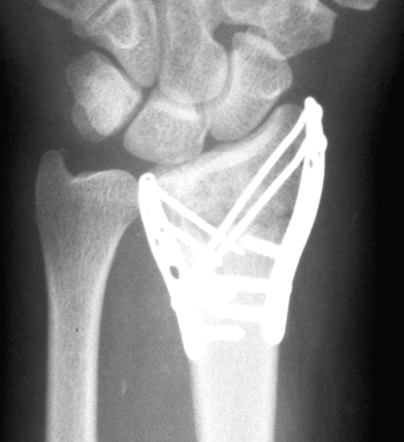

Case3 Postop